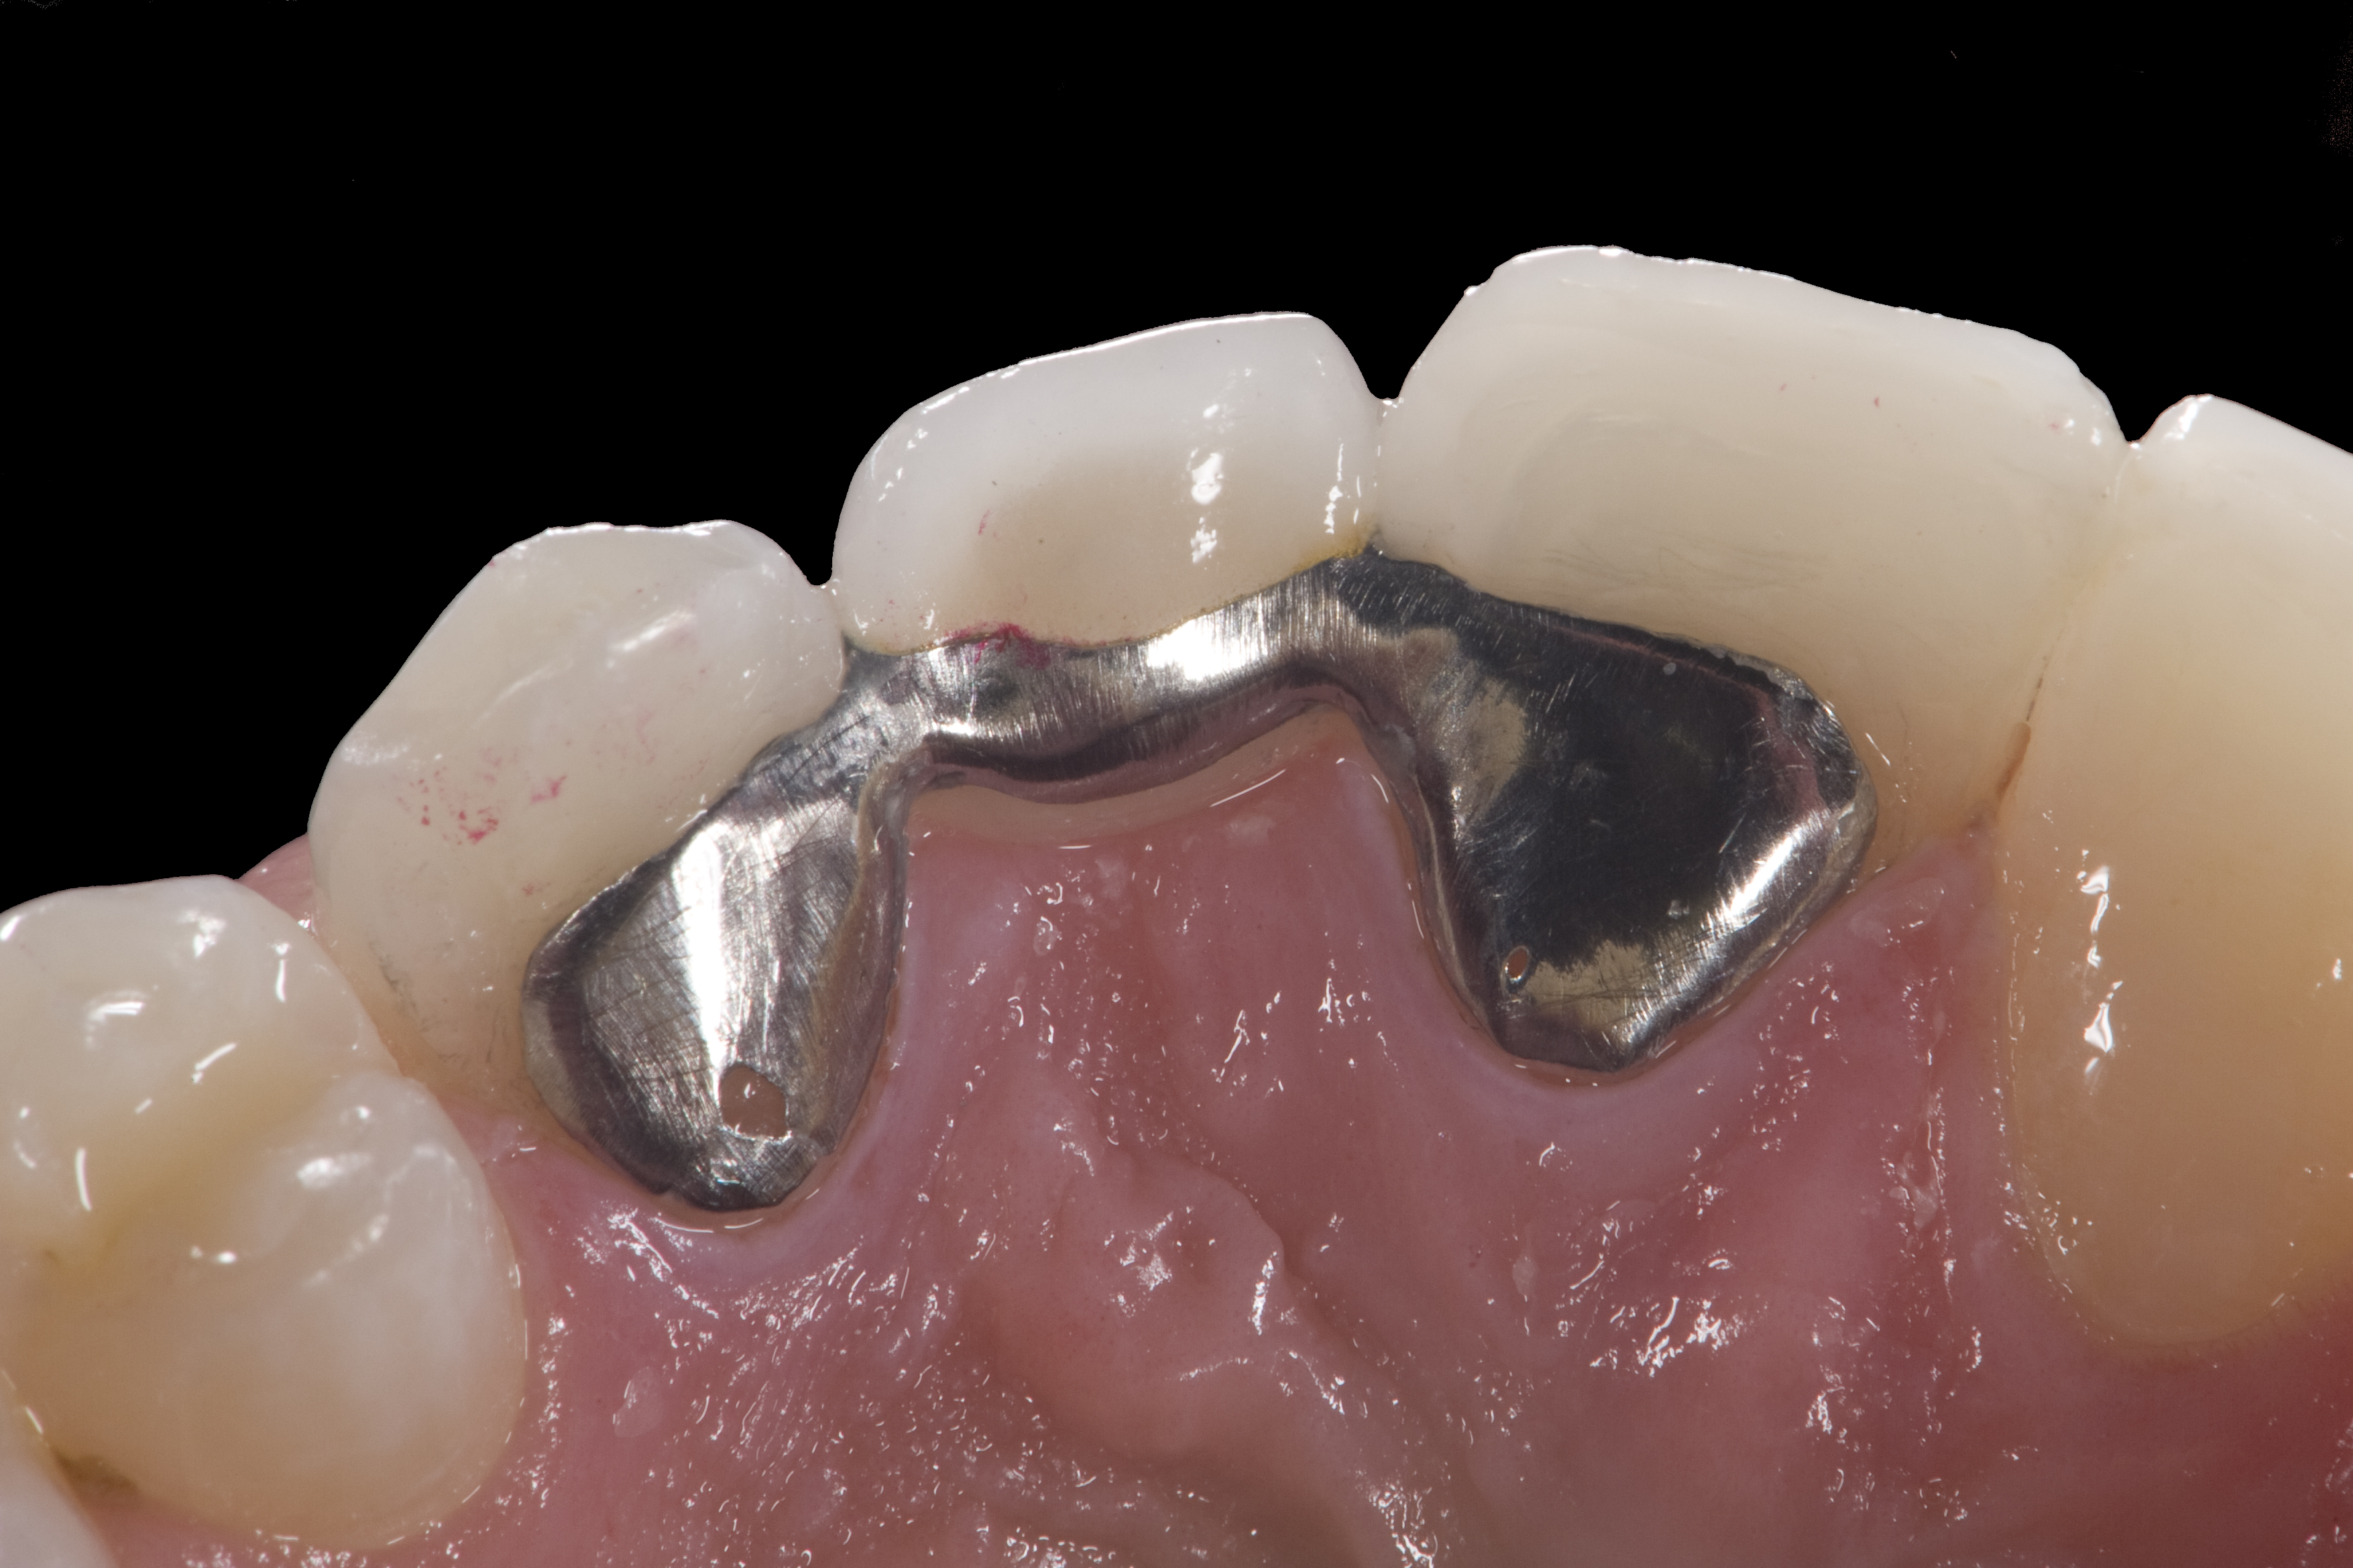

(4.) Double-wing metal resin-bonded (Maryland) bridge replacing the right lateral incisor (facial view).

Figure 4

(5.) Double-wing metal resin-bonded bridge replacing lateral incisor (lingual view).

Figure 5

A 14-year-old patient presented to the office with his mother (Figure 1). His chief complaint involved the large spaces between the teeth created by his missing right maxillary lateral incisor and his small left maxillary lateral incisor. He desired to replace the missing tooth with an implant and create a beautiful smile. Upon examination, he was found to have a class I canine and molar relationship, but because he had a tooth size/arch size discrepancy and space distal to the right central incisor, the remaining incisors had drifted to the right. The left maxillary lateral incisor was peg-shaped and in a cross bite position. Studies have shown a clear association between congenitally missing teeth and reduced tooth size.59-62 Because he was only 14 years old at the time and could not have implants placed until the cessation of growth (somewhere in the vicinity of 22 years old), he was sent to the orthodontist for alignment of the teeth.16,17 After 2 years of orthodontics, the appliances were removed, and his tooth coloration was improved using carbamide peroxide bleaching (Figure 2). Because some form of provisional needed to be placed until he was finished growing, a double-wing metal resin-bonded bridge was chosen. As discussed earlier, this is the ideal transitional prosthesis for patients that have congenitally missing maxillary lateral incisors. The benefits of this type of prosthesis include its ability to be removed and rebonded during the surgical phase of treatment and its ability to retain the roots in their proper position after orthodontic treatment.16 The final plan for the patient was to increase the width of the central and the maxillary left lateral incisor, utilizing porcelain laminate veneers to achieve the appropriate width/length ratio of 80%. A wax-up was created to idealize tooth size, a putty matrix was made from the wax-up to facilitate bonding of the incisors, and a non-precious, double-wing metal resin-bonded bridge was fabricated for lateral incisor replacement. Once the teeth were bonded to ideal size, the “Maryland Bridge” was fabricated from a polyvinyl arch impression with the newly bonded teeth (Figure 3). The metal frame was cast from a non-precious alloy to allow for fabrication of a very thin frame and to create a better surface for bonding. After sandblasting the internal aspect of the frame with CoJet™ silica (3M ESPE), accomplishing salinization, and executing cementation with a dual-cure resin cement, a fairly good adhesion to the frame was anticipated.29 The enamel surface was etched with phosphoric acid for 30 seconds, the primer (Single Bond Plus, 3M ESPE) was applied to both the internal surface of the sandblasted framework and the etched enamel, and the bridge was cemented with RelyX™ ARC (3M Espe) dual-cured resin cement (Figure 4 and Figure 5).